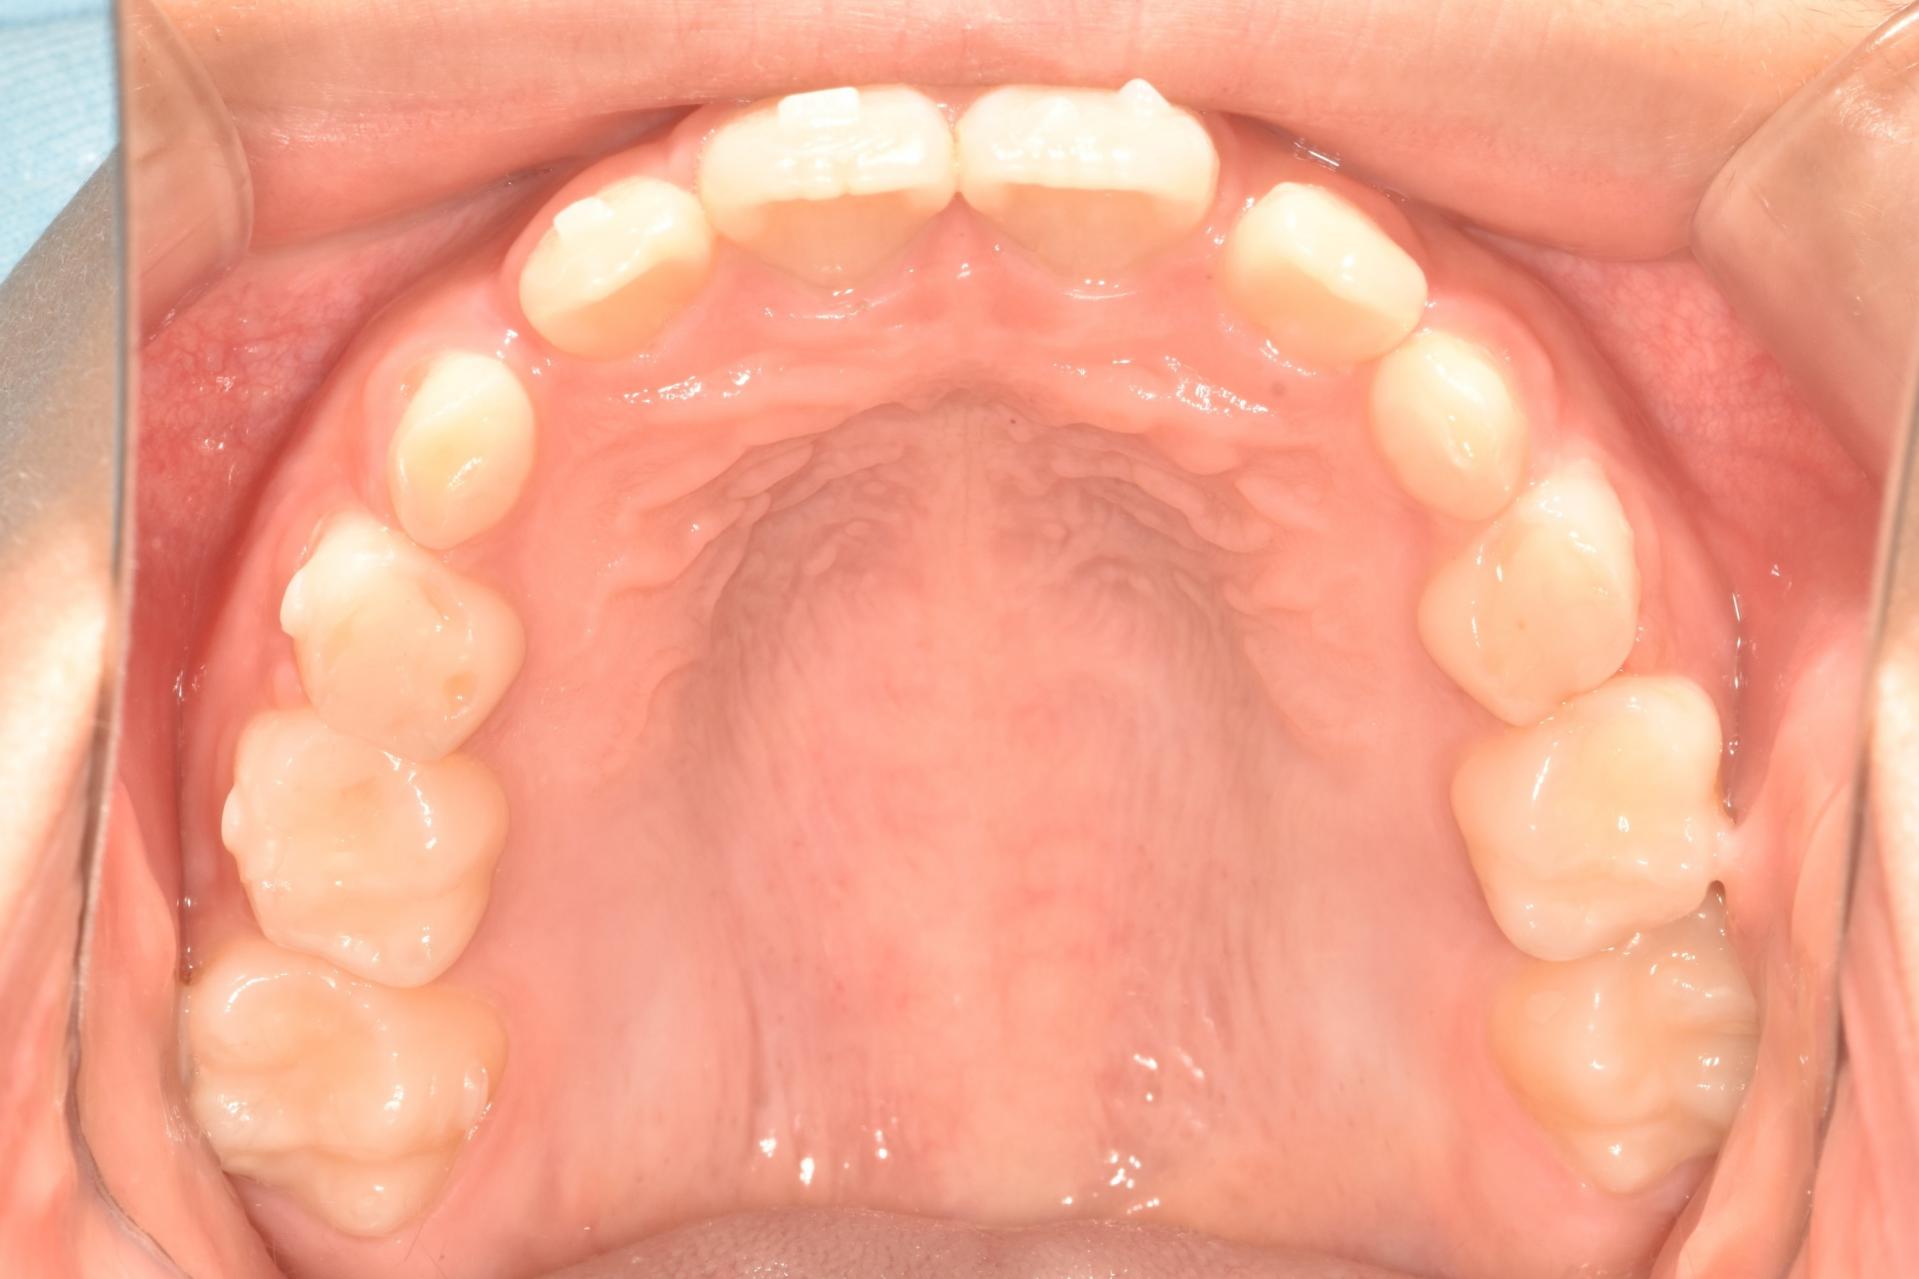

치아 사이충치를 레진으로 8개 치료, 아래 어금니 하나는 지르코니아 크라운으로 치료한 제 큰아이 입니다. (아이에게 동의를 구하고 올립니다.ㅎㅎ)

저희 큰 딸은 유치를 모두 수면치료로 치료한 후 , 지금까지 관리 잘하며 아무 탈 없이 지내고 있고, 초등학생이 되어 유치 뒤로 영구치가 4개 났는데 역시 충치가 생겨^^; 다행히 어린시절 힘든 치과치료의 기억이 없어 큰 치과 트라우마 없이 수월하게 웃음가스 만으로 치료 잘 해주었답니다. 지금은 대부분의 유치를 잘 뺴고 영구치로 예쁘게 교환했습니다.